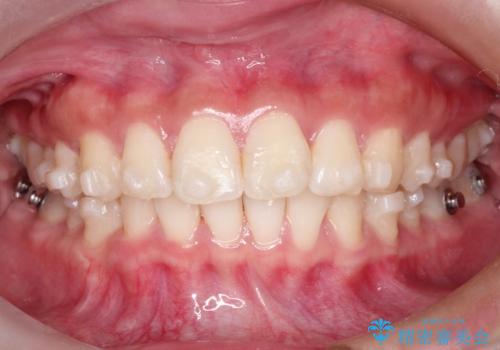

- 矯正装置

- インビザライン

- 前歯の捻れと口元の突出を主訴に来院されました。

インビザラインを用いて上顎の遠心移動を行い、前歯を下げながら凸凹を綺麗に治すことができました。

歯を抜かない矯正治療を行う場合、口元は極端には変わりません。

今回は奥歯の遠心移動を行い、できる限り前歯を下げられるように治療を行いました。